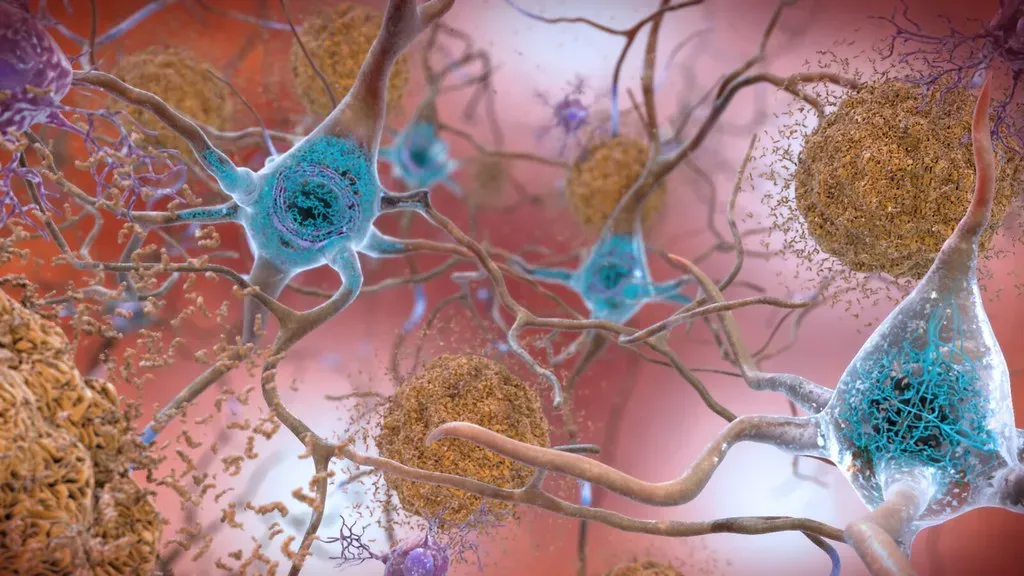

What Each Single Synapse Actually Does

Here’s something most people don’t realize. When you picture a synapse, you might imagine a simple on-off switch. That’s completely wrong. One synapse, by itself, is more like a microprocessor – with both memory-storage and information-processing elements – than a mere on/off switch. In fact, one synapse may contain on the order of 1,000 molecular-scale switches. That’s an enormous amount of computing power packed into something you couldn’t see with the naked eye.

Synapses are the spaces over which neurons send and receive electrical and chemical signals. The brain’s magical ability to learn, and to recall information already learned, depends on synapses. Researchers at the Max Planck Institute have gone even deeper into this. The research team identified more than 1,800 unique synapse type-enriched proteins, revealing a stunning diversity of molecules that underlie synaptic connections. So not only are there an almost incomprehensible number of synapses – each one is itself a universe of molecular complexity.